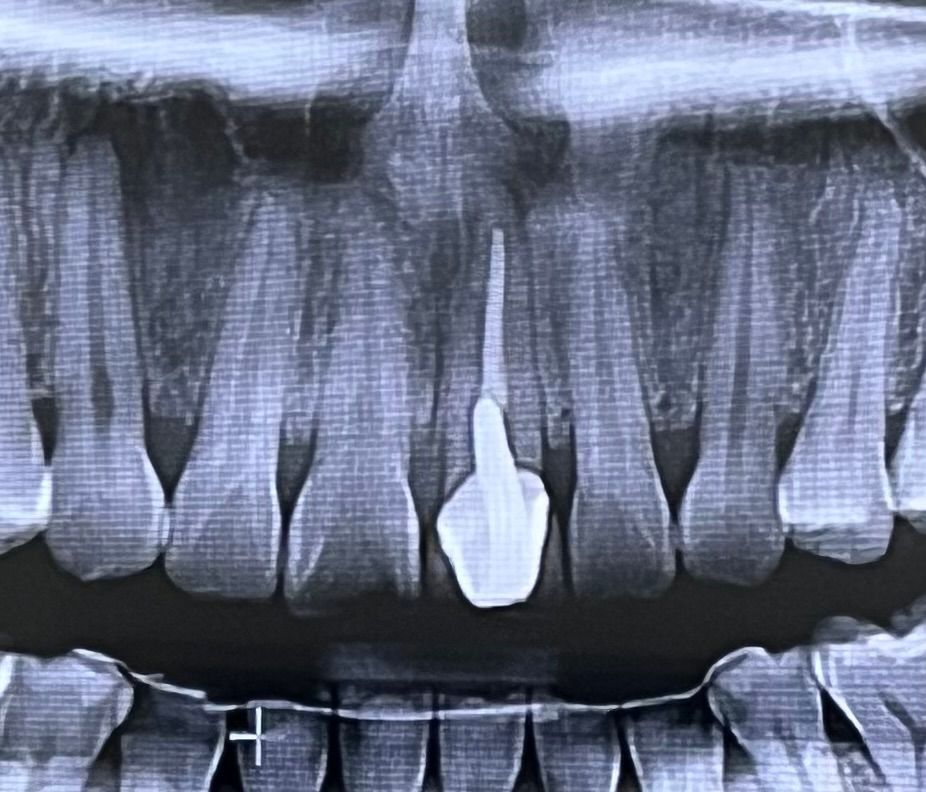

왼쪽 앞니는 어릴 때 크라운했습니다 . 현재 20년 넘게 유지중입니다 . 불편감도 없어요. 외적으로는 치아-잇몸라인이 검게 변한 것뿐입니다.

최근에 사랑니 발치를 위해 방문한 병원2에서는 크라운한 치아 위쪽에 염증이 큰 범위로 있다하시네요 ㅠㅠ 발치에 대한 두려움으로 경황스러워

발치하고 임플란트에 대한 얘기도 하셨어요 .

아직 젊은데 임플란트라니.. 크라운을 너무 오래 사용해서 그런걸까요..?